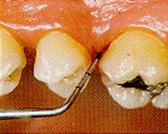

| 5:

Cavidad detectable con dentina

visible, hasta la mitad de la superficie |

| 6:

Cavidad detectable extensa con dentina visible,

más de la mitad de la superficie |